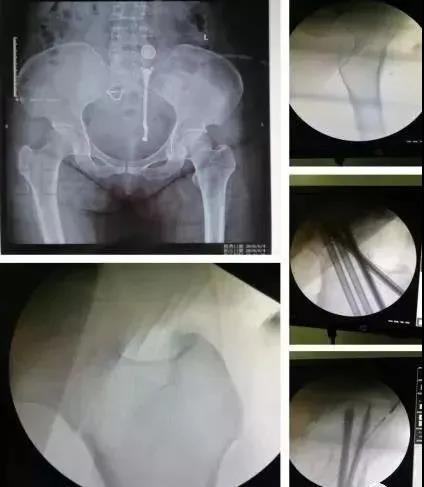

3)髋臼骨折(伤后5-7天)

- 人体最大的负重关节,精确复位可达到关节的最佳匹配,确保正常力学性能;

- 影像学移位程度大,不匹配>2mm--手术;

- 髋关节脱位,髋臼后壁骨折并股骨头骨折,复位后关节仍然不稳,或关节腔有游离骨块--手术。

并发症:异位骨化18-90%;股骨头坏死3-9%